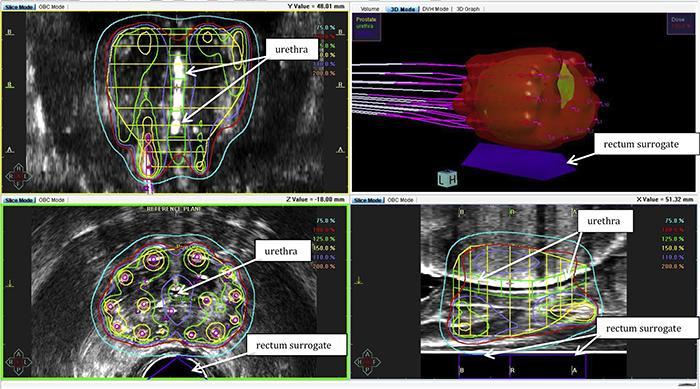

If the psa starts to rise again after it has gone down to zero or close to zero, this may signal that the prostate cancer has returned. Recurrent prostate cancer after surgery when prostate cancer shows signs of returning after primary treatment with prostatectomy, decisions about additional treatment depend in part on whether or. A recurrence means that the cancer has come back, either in the same place where it originally developed or elsewhere in the body. The urethra passes through the center of the gland from the bladder to the penis. Dysuria is an important symptom because it can indicate that something may be pressing against urinary tract, most likely an enlarged prostate, a symptom of prostate cancer.